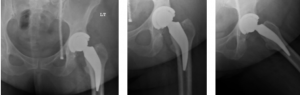

A 63-year-old Caucasian female weighing 244lbs diagnosed with osteo/degenerative arthritis received Advita’s Alteon Neck Preserving stem with a Bioloxdelta femoral head and InteGrip acetabular shell. The patient went under spinal anesthesia using a direct anterior surgical approach with an incision size of 9cm. There was an estimated blood loss of 200cc and surgery duration was 80 minutes. The patient was discharged after one day postoperative with a walker to in home care for rehabilitation.

Pre-Op AP Pelvis

Harris Hip Score 31 (max=100) | Oxford Hip Score 9 (max=48)

6-Week Post-Op

Harris Hip Score 68 (max=100) | Oxford Hip Score 38 (max=48)

3-Month Post-Op

Harris Hip Score 84 (max=100) | Oxford Hip Score 37 (max=48)

1-Year Post-Op

Harris Hip Score 100 (max=100) | Oxford Hip Score 46 (max=48)

CONCLUSION

Pre-op, this patient presented with low Harris Hip and Oxford Hip scores. The direct anterior approach used in her surgery has been associated with faster functional recover than the posterolateral approach, and one-year post-op, her scores increased by more than 69.0 percent on the Harris Hip and 80.4 percent on the Oxford Hip. The patient is satisfied with her total hip replacement, and her surgical outcomes continue to be followed on an annual basis. •